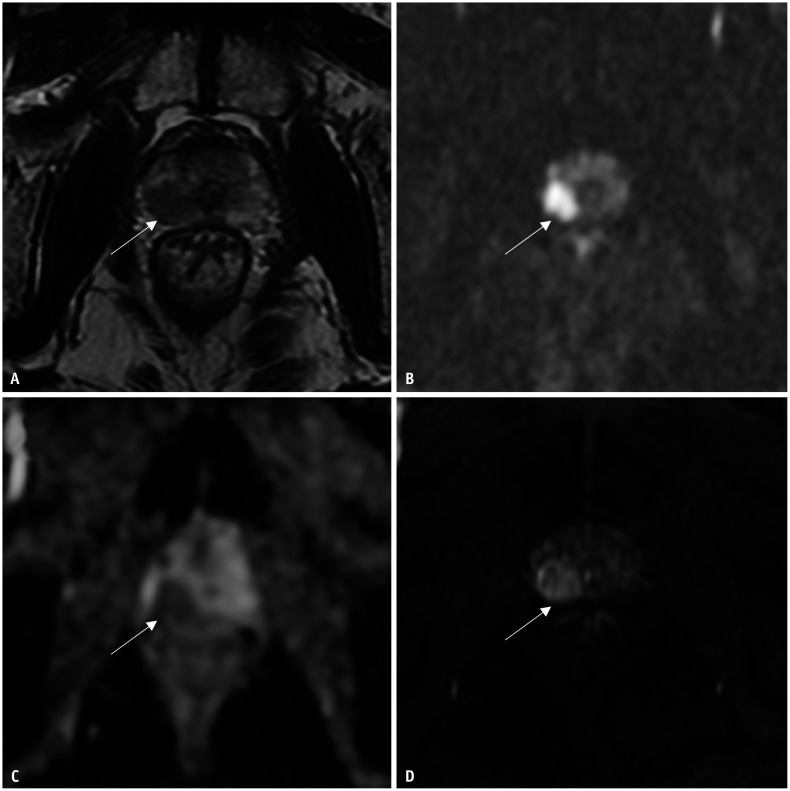

Materials and methods: Clinical and mpMRI data were retrospectively collected from 219 patients with prostate disease between January 2015 and December 2021. All patients underwent systematic prostate biopsy followed by RP. MpMRI included conventional diffusion-weighted and dynamic contrast-enhanced imaging. Multivariable logistic regression analysis was performed to analyze the factors associated with GS upgrading and downgrading after RP. Receiver operating characteristic curve analysis was used to estimate the area under the curve (AUC) to indicate the performance of the multivariable logistic regression models in predicting GS upgrade and downgrade after RP.

Abstract Image